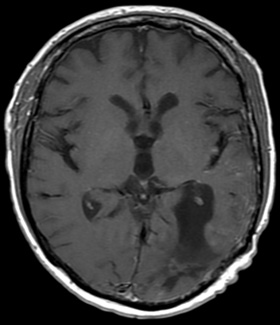

• Homme, 49 ans

• Tumeur germinale non séminomateuse du testicule droit de mauvais pronostic en 1998 avec méta hépatique et ganglionnaire, traité par CT (Endoxan, Adriamycine et Cisplatine) + chirurgie

• Récidive en  2000 avec métastase cérébrale hémorragique occipito-pariétale gauche révélée par sdr. confusionnel, traité par Radiothérapie (55 Gy) et Chimiothérapie POMBEPI (MTX, Oncovin, Bleoxycine, Cisplatine puis VP16-Ifosfamide et Cisplatine)

• 2008 crise partielle (aphasique), résection complète. Traitement par Dépakine et Urbanyl

• Rémission depuis